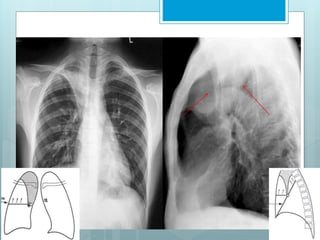

RUL Collapse

 RUL collapses toward ant, sup &

medial portion of chest.

 Medial collapse may mimic a right

paratracheal mass

 Lateral collapse lead to peripheral

mass-like opacity mimicking a

loculated pleural effusion.

 Right middle & lower lobes hyper

expand superiorly & medially.

Signs Of RUL Collapse

 S Sign of Golden.

 Juxta-phrenic peak sign.

S Sign of Golden - Refers to reverse

"S" shape of minor fissure in RUL

collapse due to a central obstructing

mass. Sup portion of "S" form displaced

minor fissure, while inf. portion results

from mass itself.

Juxtaphrenic

Peak - triangular

opacity

sometimes seen

over medial

portion of

diaphragm. Also

seen in cases of

RUL lobectomy.

Results from

superior

displacement of

inferior accessory